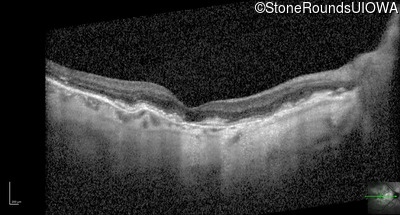

Optical Coherence Tomography - Right - 20/20 -1

Exemplar / OCT Stack

OCT Stack